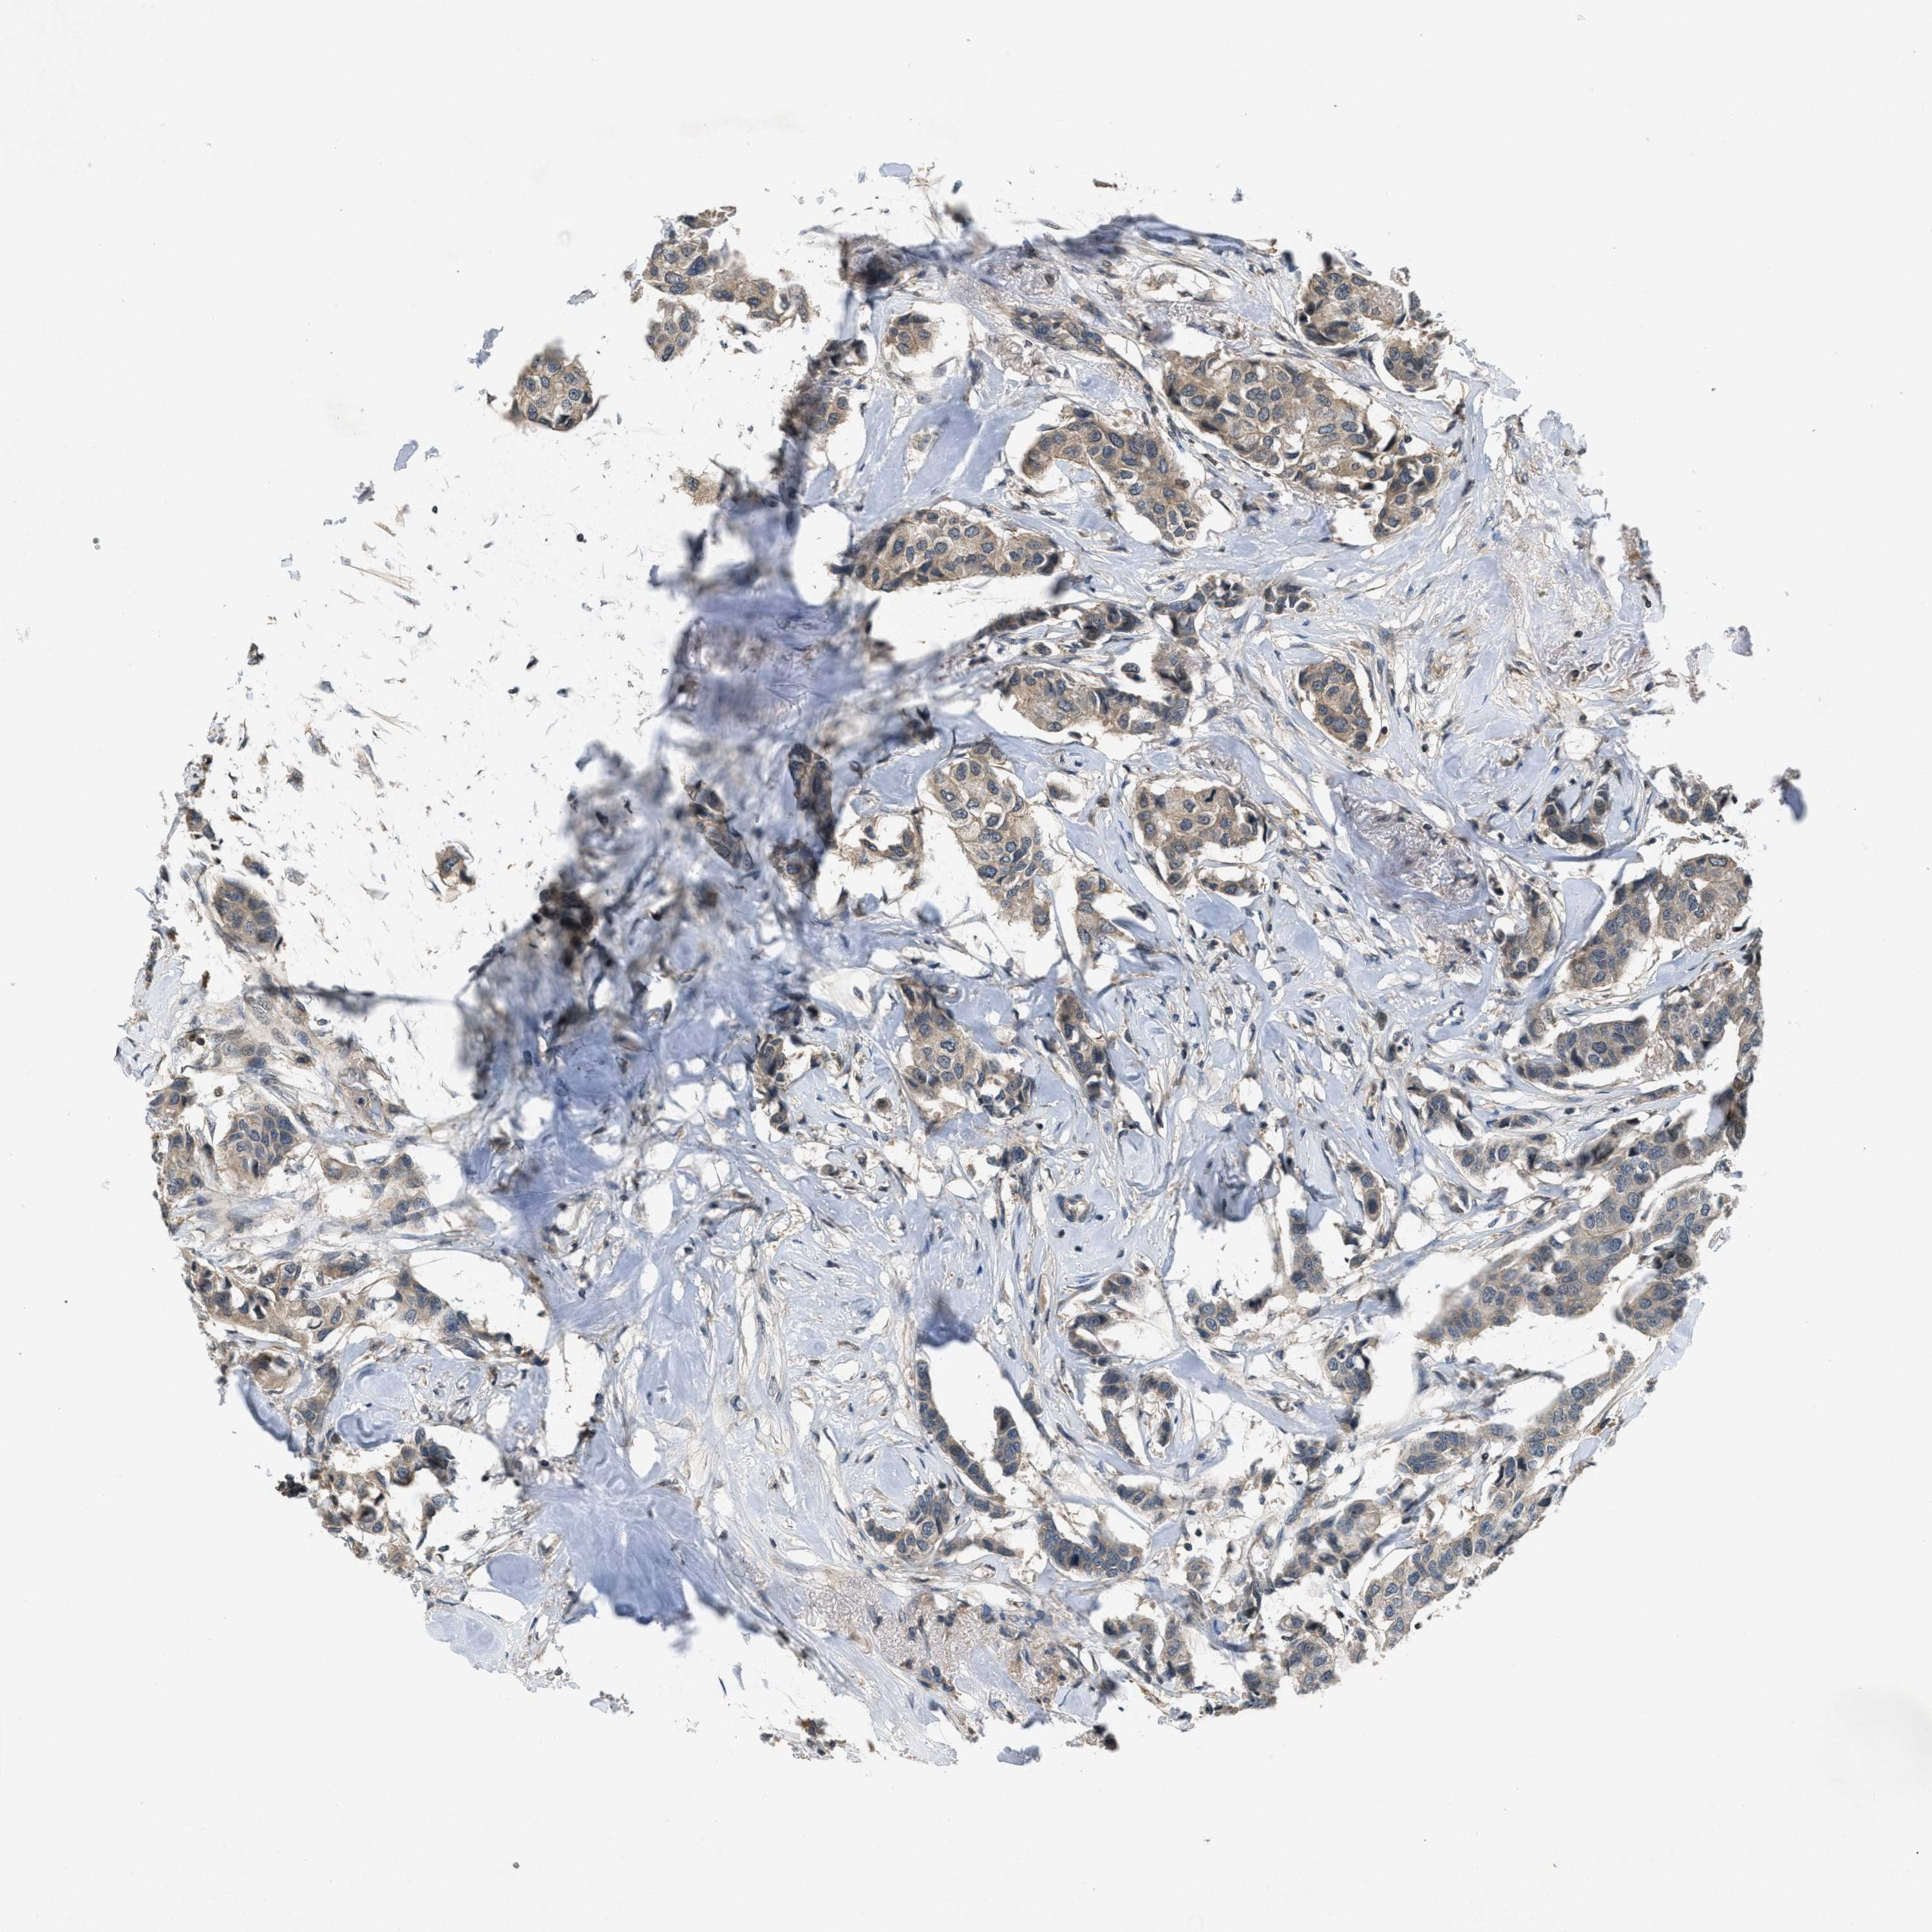

BRCA TCGA BRCA VALIDATION PROTEIN EXPRESSION

ANTIBODIES

AND

VALIDATION